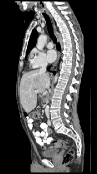

It is prudent to ask whether moving from double precision to single precision on the GPU introduces differences due to rounding. In fact, we observed that this can have an effect (Figure 1). However, it typically only occurs when there are no clear correspondences, such as in regions of the colon with different content, or when the examination table is visible in one of the two scans. In these areas, there is no strong objective function gradient in either direction during optimization, so that numerical differences have a larger impact. However, we argue that if such areas were to be registered accurately, a more elaborate model that accounts for the possible removal of structures would have to be employed in any case.